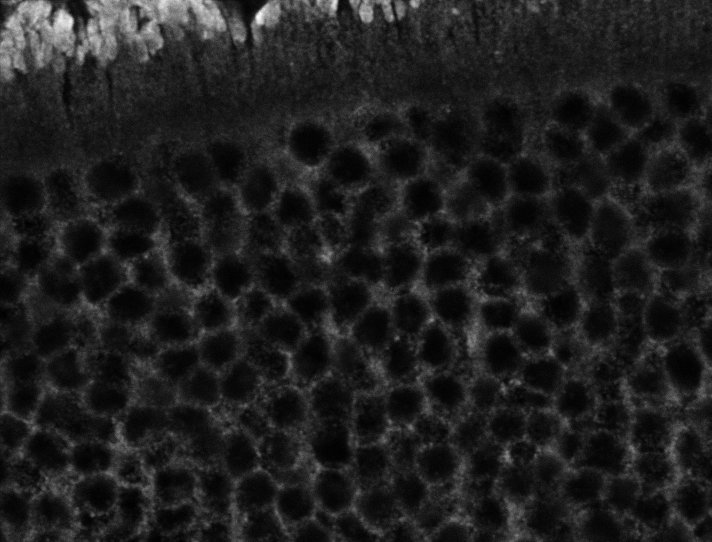

Unhealthy Choroid